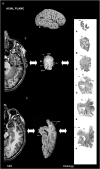

The temporal pole (TP) is the rostralmost portion of the human temporal lobe. Characteristically, it is only present in human and nonhuman primates. TP has been implicated in different cognitive functions such as emotion, attention, behavior, and memory, based on functional studies performed in healthy controls and patients with neurodegenerative diseases through its anatomical connections (amygdala, pulvinar, orbitofrontal cortex). TP was originally described as a single uniform area by Brodmann area 38, and von Economo (area TG of von Economo and Koskinas), and little information on its cytoarchitectonics is known in humans. We hypothesize that 1) TP is not a homogenous area and we aim first at fixating the precise extent and limits of temporopolar cortex (TPC) with adjacent fields and 2) its structure can be correlated with structural magnetic resonance images. We describe here the macroscopic characteristics and cytoarchitecture as two subfields, a medial and a lateral area, that constitute TPC also noticeable in 2D and 3D reconstructions. Our findings suggest that the human TP is a heterogeneous region formed exclusively by TPC for about 7 mm of the temporal tip, and that becomes progressively restricted to the medial and ventral sides of the TP. This cortical area presents topographical and structural features in common with nonhuman primates, which suggests an evolutionary development in human species.